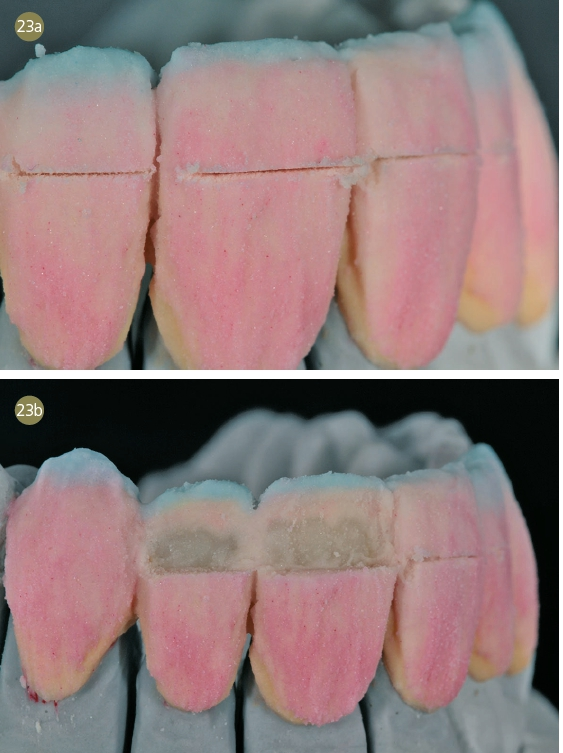

Nach der Farbbestimmung unter Zuhilfenahme eines Kreuzpolfilters und individueller Farbmusterplättchen wurden die Frontzähne minimalinvasiv präpariert (Abb. 3a–c, Abb. 4).

Die Veneerschalen wurden virtuell konstruiert (Abb. 5) und nach dem Nesten (Abb. 6) aus ultratransparentem dima HTE-Material in einer Wandstärke von 0,4 mm gefräst. Für das CAM steht uns unsere Cara DS mill 3.5 zur Verfügung (Kulzer). Die noch nicht gesinterten Zirkoniumdioxidkäppchen arbeiteten wir nach dem Heraustrennen nur noch mit einem speziellen Hochleistungsbohrer aus.

Nach dem Sintern wurden die Gerüste auf Passung kontrolliert und wir dünnten die Ränder unter dem Mikroskop aus. Im Anschluss wurden die Objekte unter 2 bar Druck mit 120 ?m Aluminiumoxid vorsichtig abgestrahlt.